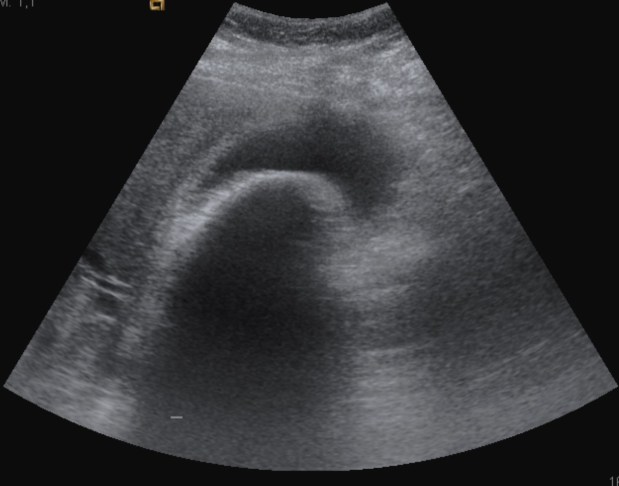

Paciente de 67 años que acude a urgencias con dolor de varias horas de evolución, localizado en epigastrio e hipocondrio derecho. Fiebre de 38,1ºC. Murphy positivo. Analítica: Leucocitosis con neutrofilia.

Se realiza ecografía abdominal:

Con estos hallazgos ecográficos podemos concluir que el paciente presenta una COLECISTITIS AGUDA.